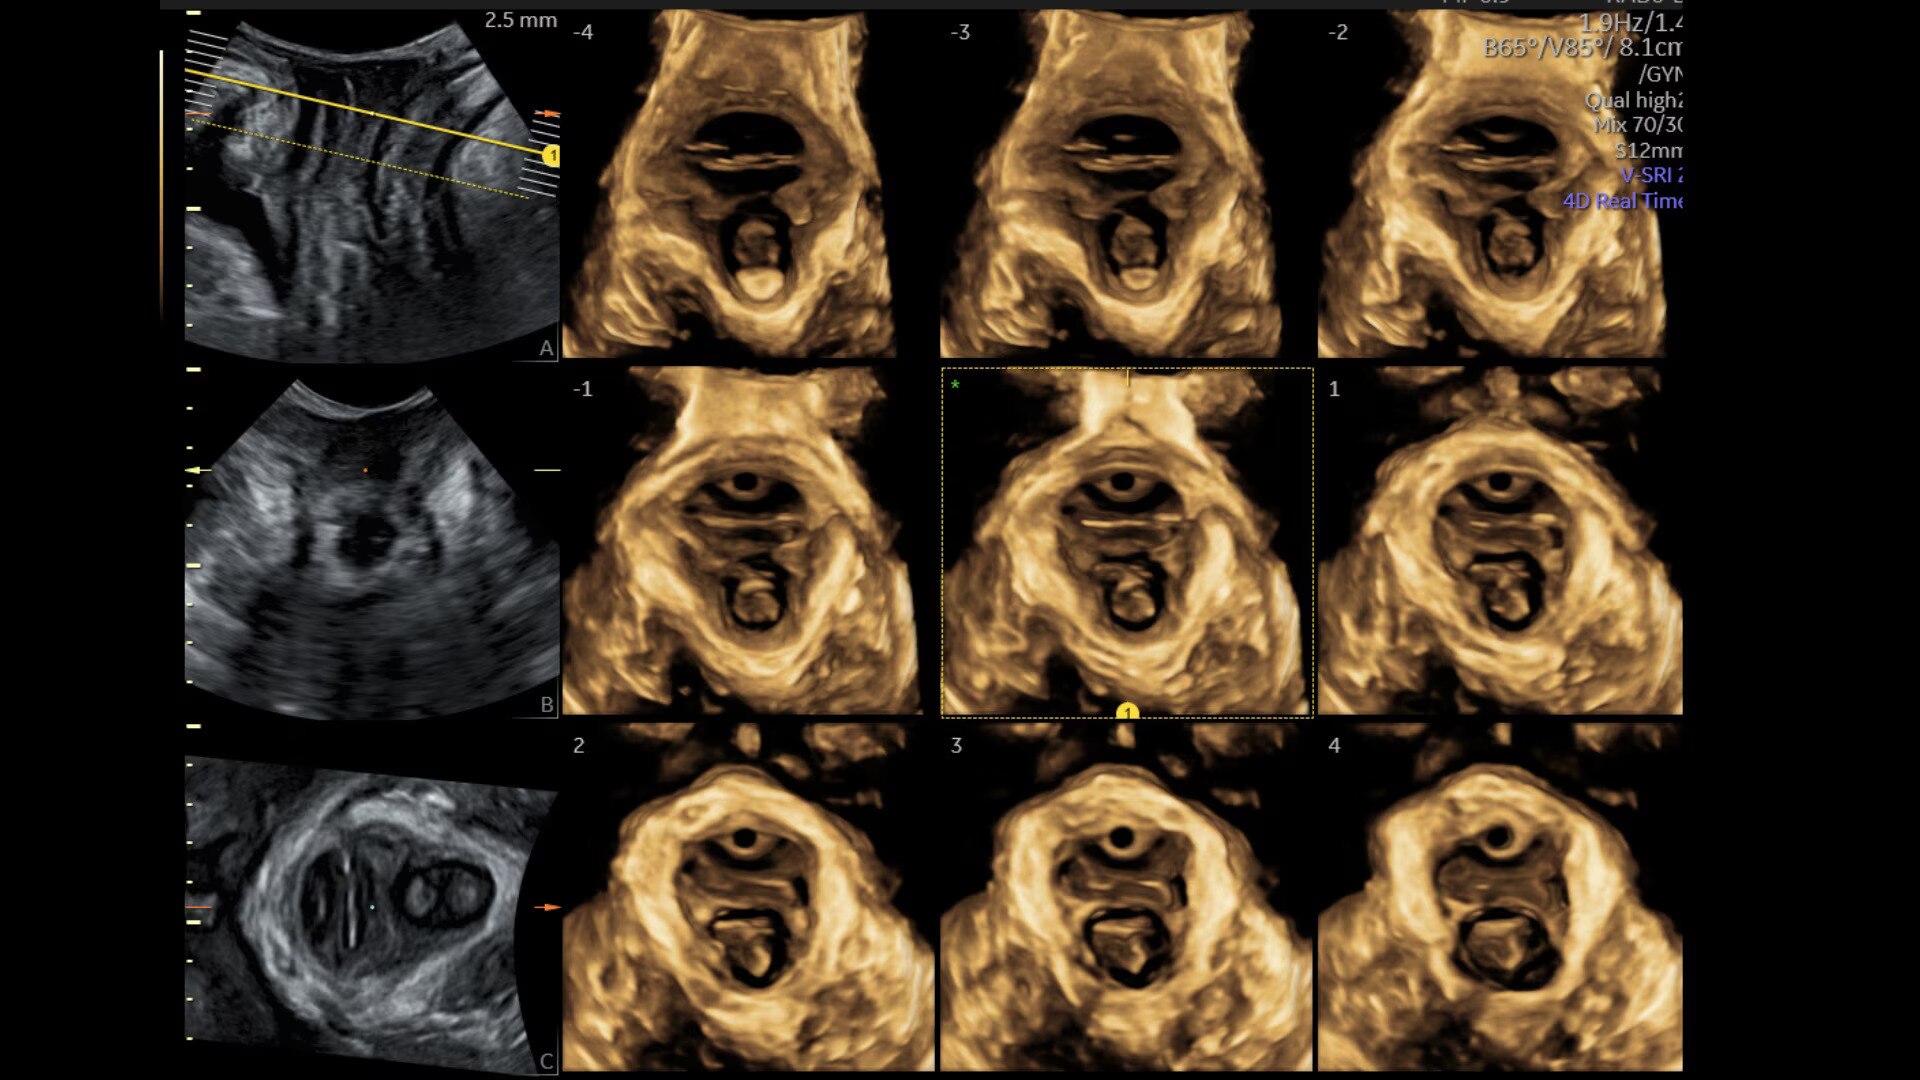

Assess pelvic floor anatomy using guided workflow & AI

Using a guided workflow and AI, SonoPelvicFloor:

• removed exam complexity by automating plane alignment and measurements

• can reduce keystrokes by up to 75% and offer users a time savings of up to 80%